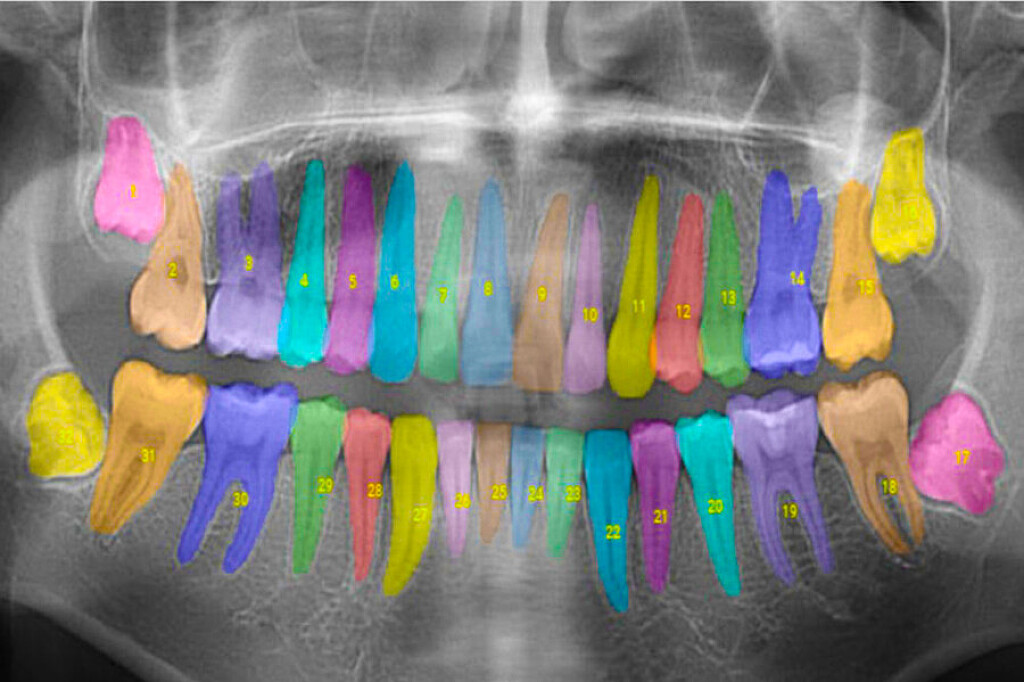

Taking the guesswork out of dental care with artificial intelligence MIT alumni-founded Overjet analyzes and annotates dental X-rays to help dentists offer more comprehensive care.

Inam is the co-founder of Overjet, a company using artificial intelligence to analyze and annotate X-rays for dentists and insurance providers. Overjet seeks to take the subjectivity out of X-ray interpretations to improve patient care.

Overjet has been cleared by the Food and Drug Administration to detect and outline cavities and to quantify bone levels to aid in the diagnosis of periodontal disease, a common but preventable gum infection that causes the jawbone and other tissues supporting the teeth to deteriorate.

In addition to helping dentists detect and treat diseases, Overjet’s software is also designed to help dentists show patients the problems they’re seeing and explain why they’re recommending certain treatments.